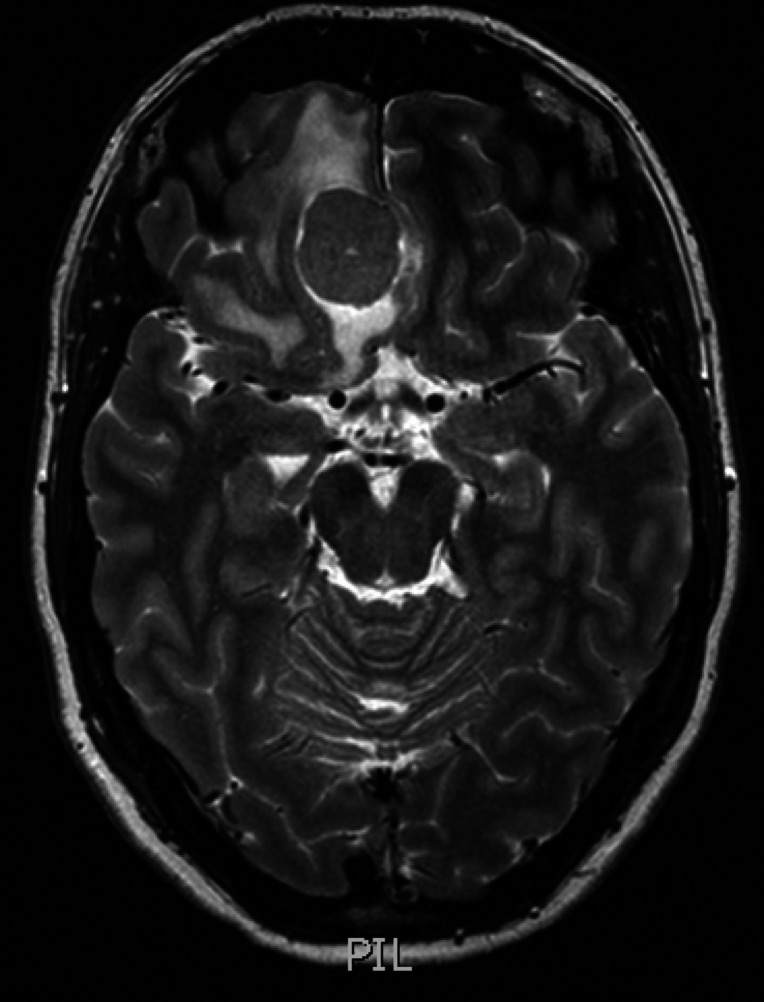

脑膜瘤3Cm严重吗? 脑膜瘤手术 后多久恢复? 脑膜瘤(Meningiomas)是一种常见的颅内肿瘤,在颅内肿瘤中占二位,是起源于脑膜及脑膜间隙的衍生物。大多数脑...

脑膜瘤是一种常见的颅内肿瘤,对人体健康危害很大。常见的治疗方法是手术切除,但术后相关的预防和护理工作也重要,可以更好地帮助患者恢复...